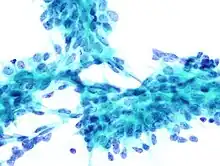

Cytology

The diagnostic findings on needle biopsy consist of abundant stromal cells, which appear as bare bipolar nuclei, throughout the aspirate; sheets of fairly uniform-size epithelial cells that are typically arranged in either an antler-like pattern or a honeycomb pattern. These epithelial sheets tend to show typical metachromatic blue on Diff-Quik staining. Foam cells and apocrine cells may also be seen, although these are less diagnostic features.[9][11] The gallery images below demonstrate these features.

Fibroadenoma, fine needle aspiration biopsy (Giemsa or DiffQuick stain). The image shows abundant bare bipolar stromal nuclei surrounding sheets of metachromatic epithelial cells. -

Fibroadenoma, fine needle aspiration biopsy (Papanicolou stain). The image shows a sheet of epithelial cells in the typical antler pattern. -